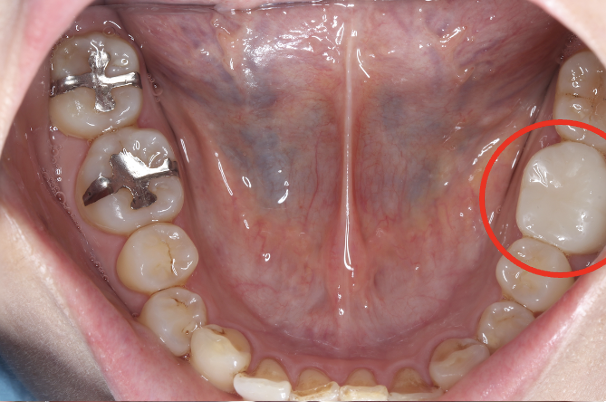

セラミック症例④

年齢50代男性

治療期間1ヶ月

治療内容セラミックインレー、クラウン

治療箇所

左下7番 左上4番、5番、7番 右下6番 右上5番

治療費用600,000円